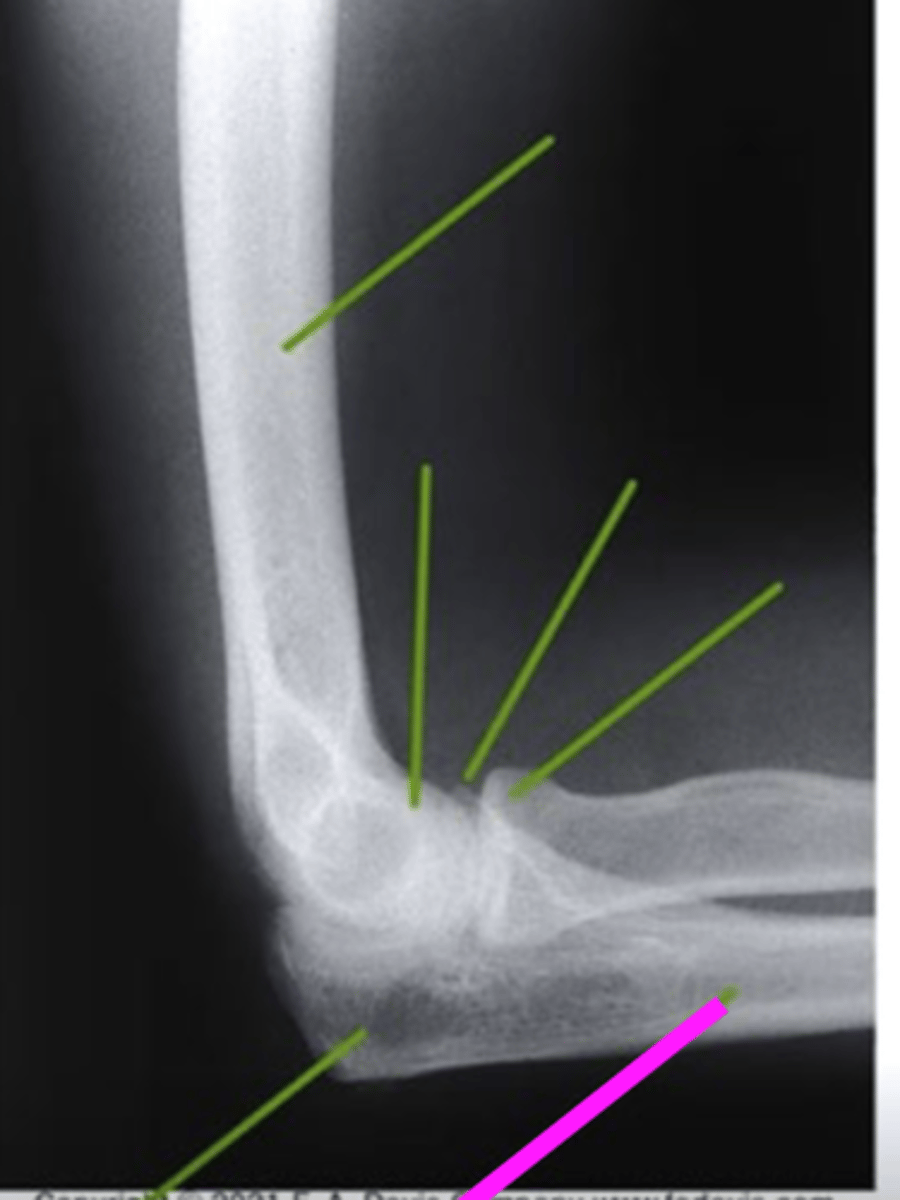

Lateral Elbow

what view is this

humerus

what does the pink line point to?

trochlear sulcus

coronoid process of olecranon

radial head

olecranon process

ulna